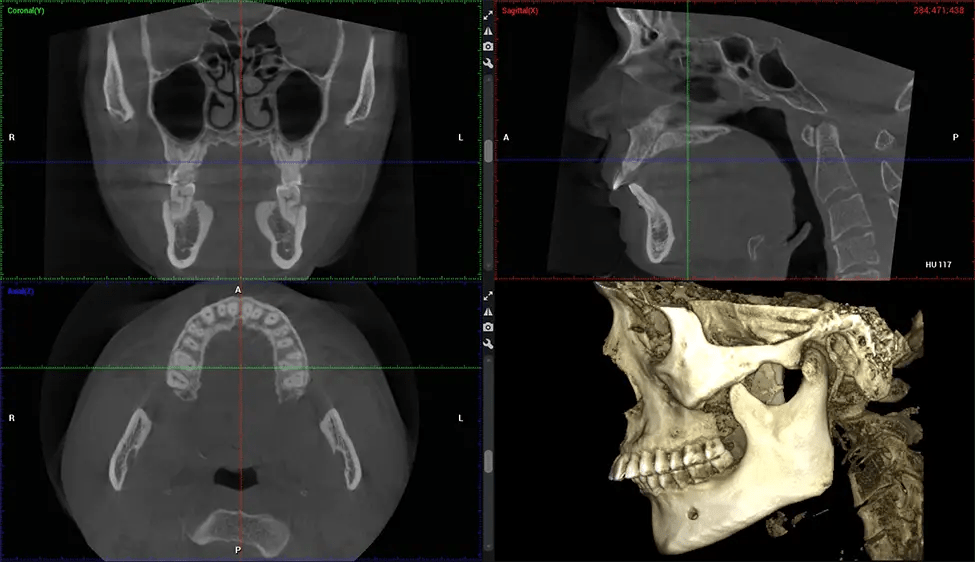

There are many benefits to using CBCT technology, especially compared to the traditional 2D X-ray format. One of the most significant advantages of CBCT scans is that they provide much more information than traditional X-rays. A scan lets your dentist see images from all angles of your jaw and mouth, including your sinuses, nasal cavity, cheekbones, and other surrounding areas. This added information helps your dentist craft a comprehensive treatment plan that addresses all aspects of your oral health.

The patient is first positioned in the CBCT scanner, which typically consists of a rotating arm that houses the X-ray source and a detector. The patient’s head is immobilized to ensure accurate image capture. The X-ray source and detector rotate around the patient’s head, capturing various X-ray images from multiple angles. As the X-ray source rotates, it emits the cone-shaped X-ray beam towards the detector. The detector captures the X-ray images, which are then processed by the CBCT software.

After the scanning process, the captured X-ray images are processed by the CBCT software, which applies algorithms to reconstruct a detailed 3D image of the scanned area. The software compiles these individual X-ray images and creates a digital 3D representation of the patient’s anatomy. The reconstructed 3D CBCT image can be viewed and analyzed by the dentist or radiologist. This image can be manipulated, rotated, and zoomed in or out to examine specific structures and evaluate the patient’s condition.